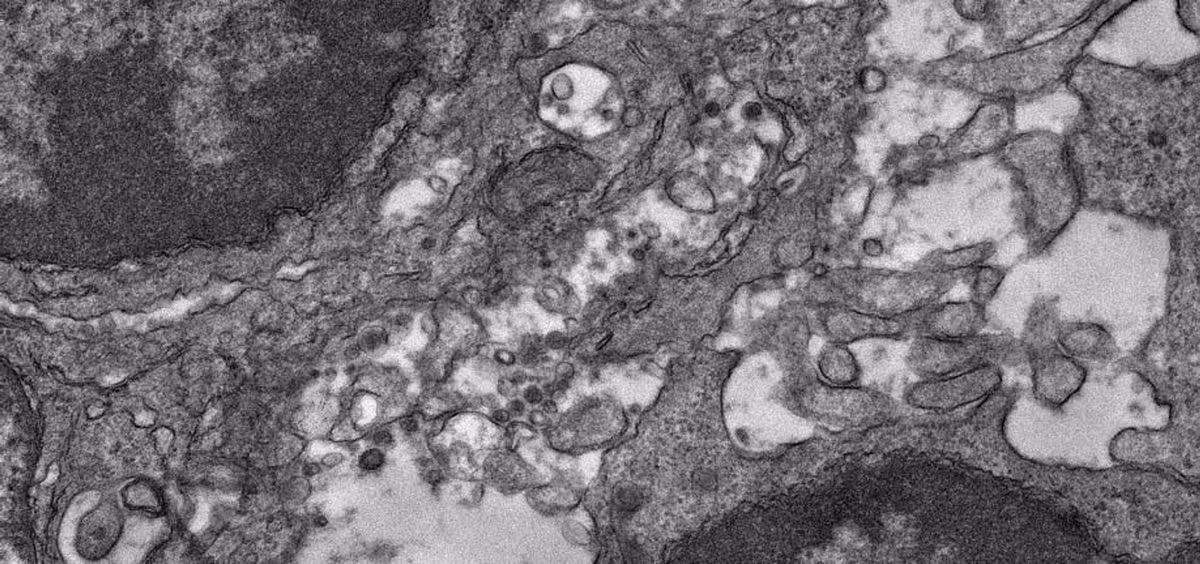

Por último, los investigadores examinaron el proceso biológico de inducción de la inmunidad, mostrando con microscopía electrónica en los ganglios linfáticos de los ratones inmunizados cómo sus partículas de la vacuna experimental se enganchan a las células dendríticas foliculares (células inmunitarias que recogen y presentan las partículas virales para ayudar a iniciar una respuesta inmunitaria robusta), así como a las células B productoras de anticuerpos.

Compararon este acoplamiento con el de un diseño de proteína de espiga suelta, y los resultados sugirieron, según varias medidas, que la nueva vacuna candidata basada en nanopartículas es muy superior en su capacidad de estimular estos elementos inmunitarios. Por ejemplo, las partículas de la vacuna basada en nanopartículas se desplegaron cuatro veces más en las células dendríticas foliculares, y estimularon respuestas de células B mucho más largas y grandes, conocidas como reacciones del centro germinal.